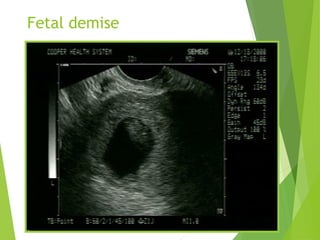

Abnormal IUP

 A GS larger than 10-13 mm diameter(TV) or 20mm (TA)

without a yolk sac

 A GS larger than 18 mm (TV) or 25mm (TA) without a

fetal pole

 A definite fetal pole without cardiac activity after 7 wks

GA

Empty gestational sac

Fetal demise